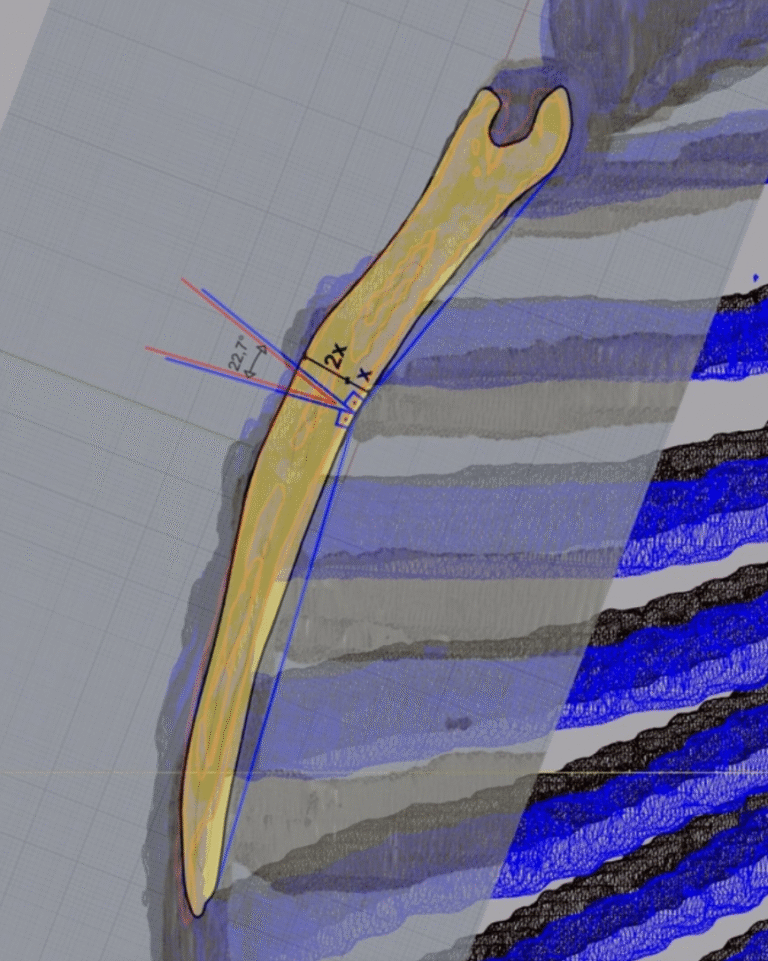

Ameliyat sırasında, sternum (iman tahtası) ile kaburgalar arasındaki düzensiz kıkırdak segmentleri çıkarılır,

ardından sternum doğru anatomik konumuna getirilir ve gerekirse destekleyici materyallerle stabilize edilir.